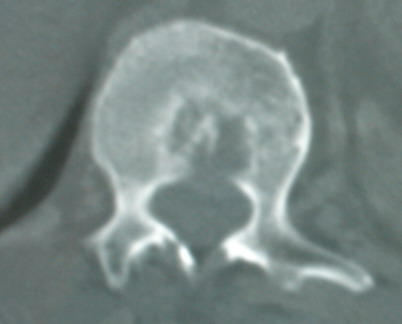

以下是引用jinguoji在2008-6-3 20:20:00的发言:[br]双上肺弥漫性小结节影,纵隔窗内钙化淋巴结影,考虑血播性tb可能性较大,不除外肺ca可能。腰椎考虑退变。